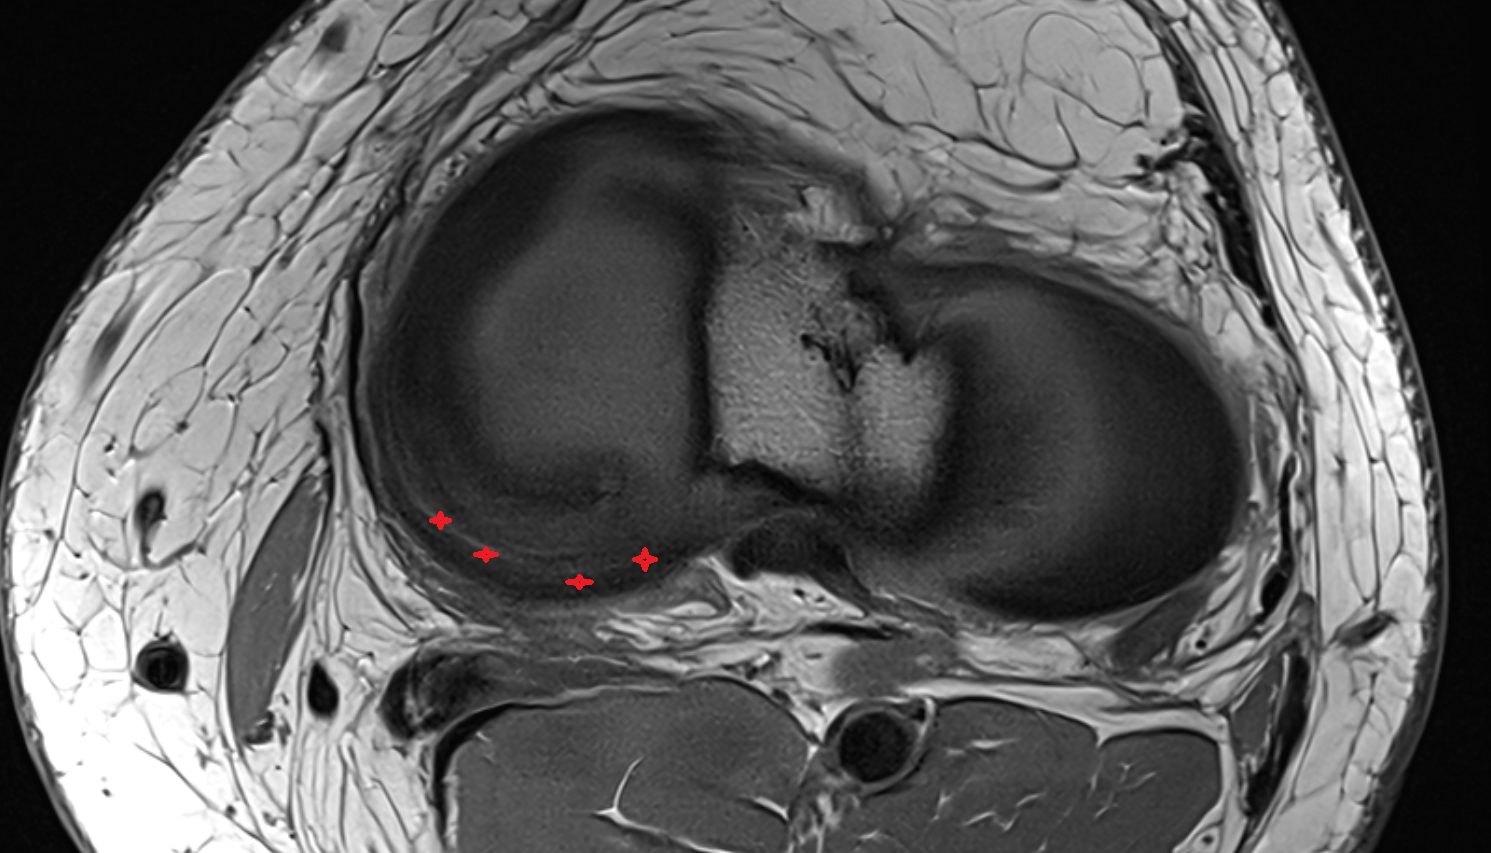

- Medial meniscus

- Lateral meniscus

- Anterior horn of medial meniscus

- Posterior horn of medial meniscus

- Body of medial meniscus

- Anterior horn of lateral meniscus

- Posterior horn of lateral meniscus

- Body of lateral meniscus

- Knee Joint